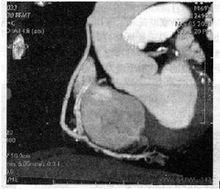

冠脈搭橋術CT圖

冠脈搭橋術CT圖心導管支架介入是治療冠心病一項很時髦的方法,治療冠心病主要有藥物治療、手術及支架介入三種方式,三種方式各有長短。服藥並不能改變血管狹窄的狀況,但藥物仍是冠